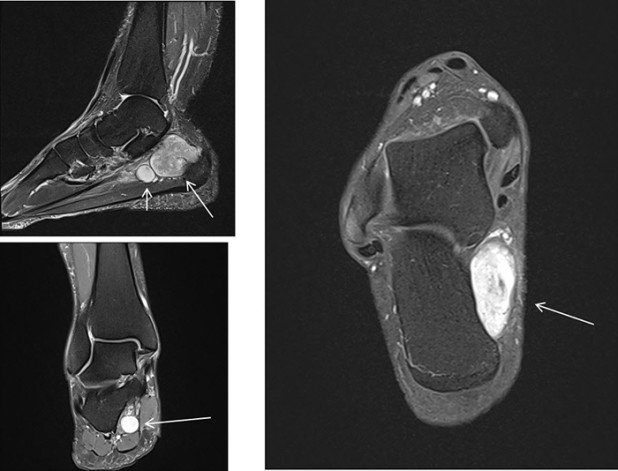

Die im Anschluss erfolgte Magnetresonanz-Untersuchung bestätigt das Vorliegen eines gutartigen Weichteiltumors, am ehesten eines Nervenscheidentumors mit scharf abgrenzbarer knotiger Raumforderung und starker Kontrastmittel-Anreicherung (Abb. 4, weisser Pfeil).

- MRI: Knotige, Kontrastmittel-aufnehmende, scharf begrenzte retromalleoläre Raumforderung mit zentraler Nekrose